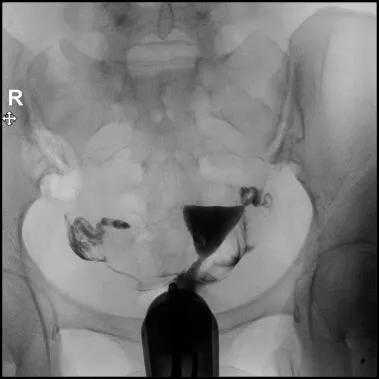

无痛动态输卵管造影是检查输卵管的最佳方法,这种方法是在消毒浸润麻醉宫颈口后将新型造影导管置入宫颈口,医生在X线监视下将对比剂经导管缓慢注入宫腔,动态观察对比剂逐渐膨胀宫腔,流入输卵管,经伞端进入盆腔的全过程。然后根据对比剂间隔时间拍摄弥散片完成检查。

3.造影检查时间为月经干净后第3-7天。月经周期较长者可适当推迟,周期短者可测BBT后在排卵前造影。

8.透视下注对比剂,动态观察造影剂逐渐膨胀宫腔,流入输卵管,经过伞端流入盆腔的全过程,同时拍摄X光片;

9.在注入对比剂后的20分钟或24小时再拍一张弥散片,观察对比剂在盆腔的弥散情况,分析宫颈、子宫、输卵管的形态特征;

充盈片

弥散片